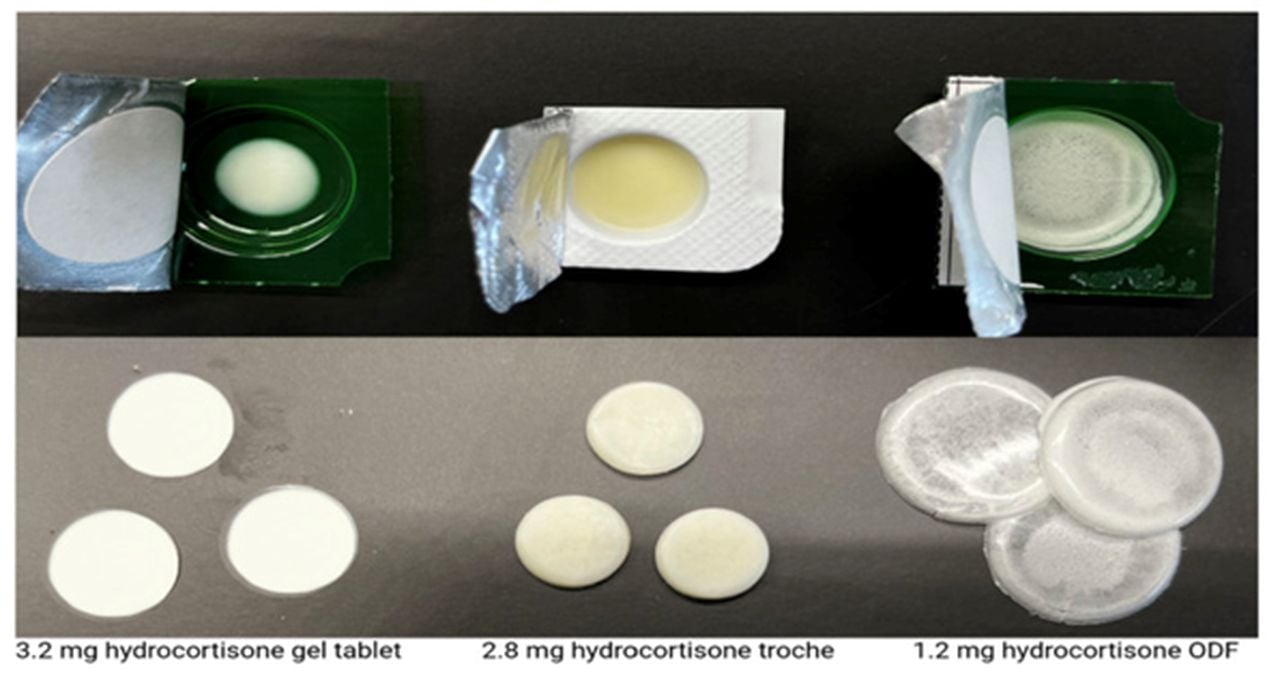

Dose by Design: Pharmaceutical 3D Printing and the Future of Pediatric Compounding

Charles R. Goulding and Andressa Bonafe highlight the shift from clinical pilot programs to everyday pharmacy practice, where 3D printing and R&D tax credits are reshaping the future of pediatric drug compounding.